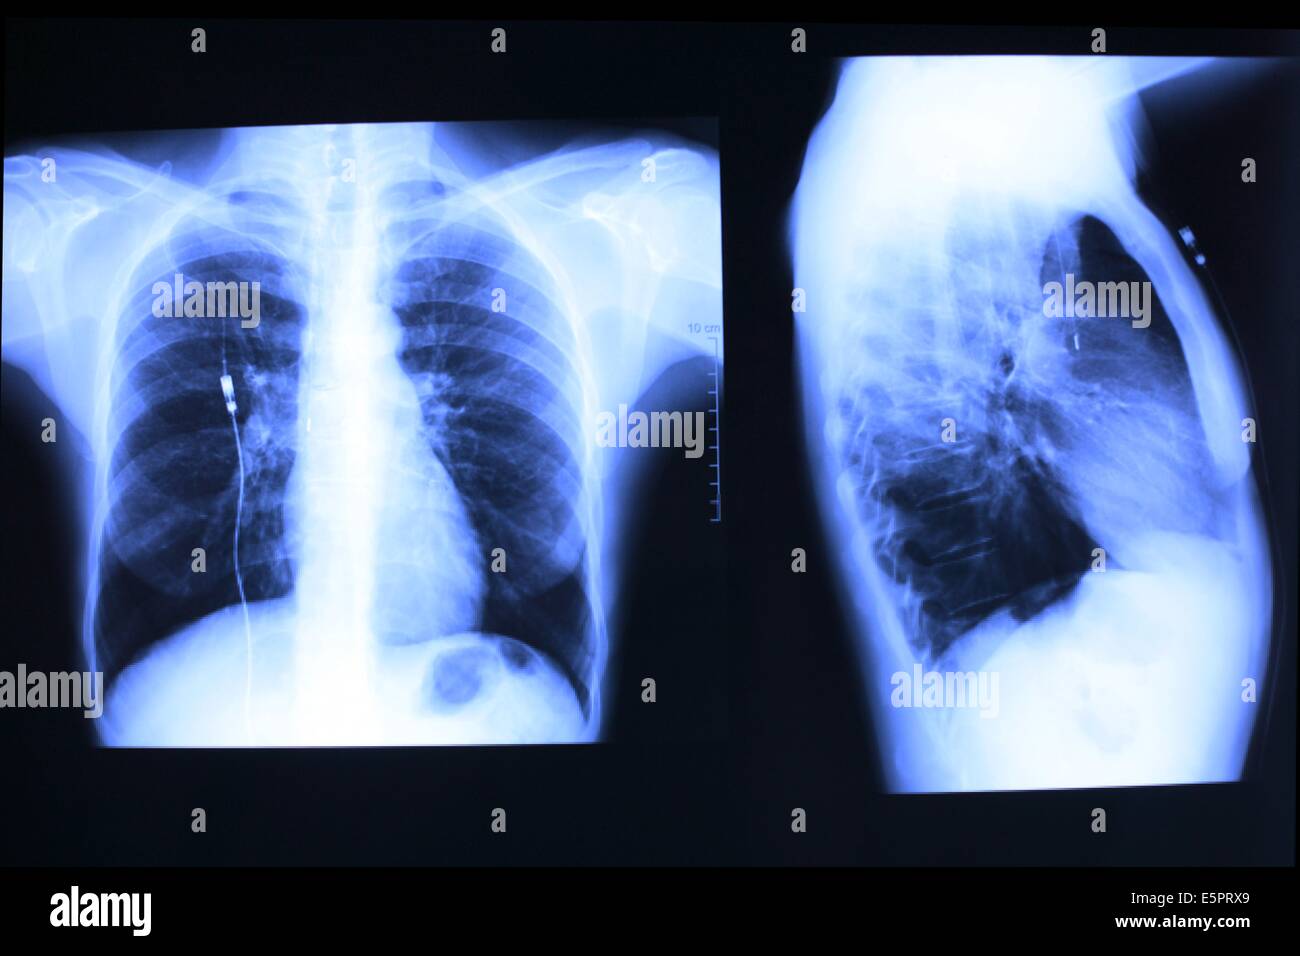

From www.e7health.com

What Do Chest XRays Show? Does A Chest X-Ray Show Pancreatitis The web page explains the 2012 revised atlanta. Imaging scans of your abdomen with. Used to look for free gas under the diaphragm (pneumoperitoneum) in patients who present with epigastric tenderness. Learn about the diagnosis, severity and complications of acute pancreatitis based on ct and mri findings. Pain consistent with acute pancreatitis) lipase / amylase. Acute pancreatitis is a sudden. Does A Chest X-Ray Show Pancreatitis.